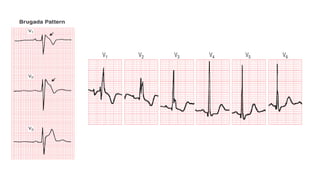

• #39 Brugada pattern showing characteristic ST elevations in the right chest leads. The ECG superficially resembles a right bundle branch block (RBBB) pattern. However, typical RBBB produces an rSR′ pattern in right precordial leads and is not associated with ST segment elevation (arrows) in this distribution. The Brugada pattern appears to be a marker of abnormal right ventricular repolarization and in some individuals (Brugada syndrome) is associated with an increased risk of life-threatening ventricular arrhythmias and sudden cardiac arrest.